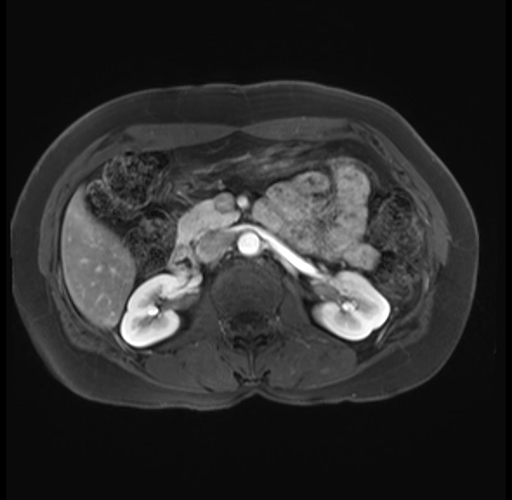

Imaging Analysis

Look through the patient's CT scan to identify any areas of concern for the necessary procedure.

Based on your CT findings, which issue(s) are present and would give reason for "planned slowing down moment(s)" in this case?

Considering a standard distal pancreatectomy procedure, what step(s) of the operation would you do differently in this case?